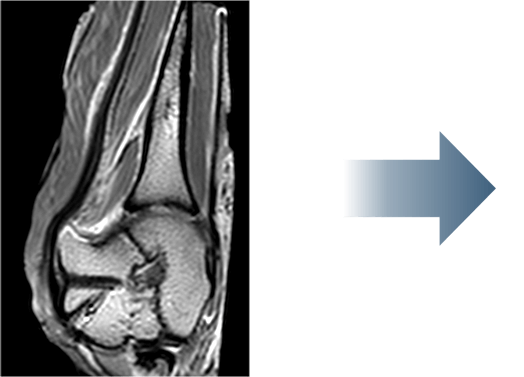

This is one of my cases, a 55-year-old woman, when her primary rotator cuff repair was done, we used Dermis on Demand, which is an allograft skin that can be utilized to help strengthen repairs. At four months out, the patient presented with pain and weakness following a traumatic injury and wound up re-tearing.

You can see a clear retear to the rotator cuff here with slight retraction, and some degeneration and thickness to the tendon.

This was not a softball case. Many aren’t. These are the complex rotator cuffs that worry you at night... Are you going to be able to fix it? Yes. But will it heal? That's the challenge. And that's where this implant helps you on a day-to-day basis.